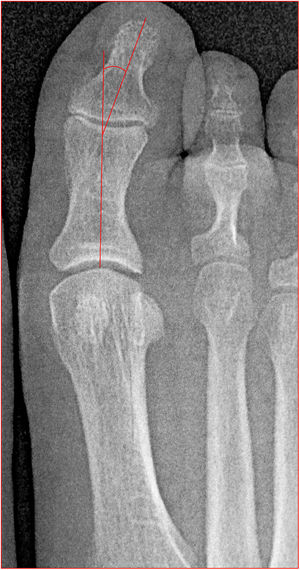

Angulo de desplazamiento articular distal (DASA por sus siglas en inglés), mide la orientación de la superficie articular de la falange proximal. Es el ángulo entre la perpendicular a la línea del eje de la falange proximal y la línea de la articulación de la falange proximal. Mayor a 10 indica deformidad en la falange (fig. 7).

Angulo de valgo interfalángico entre los ejes longitudinales de falange proximal y el primer metatarsiano, normal hasta 10. Este ángulo elevado empeora clínicamente la deformidad y requiere osteotomía de la falange (fig. 8).